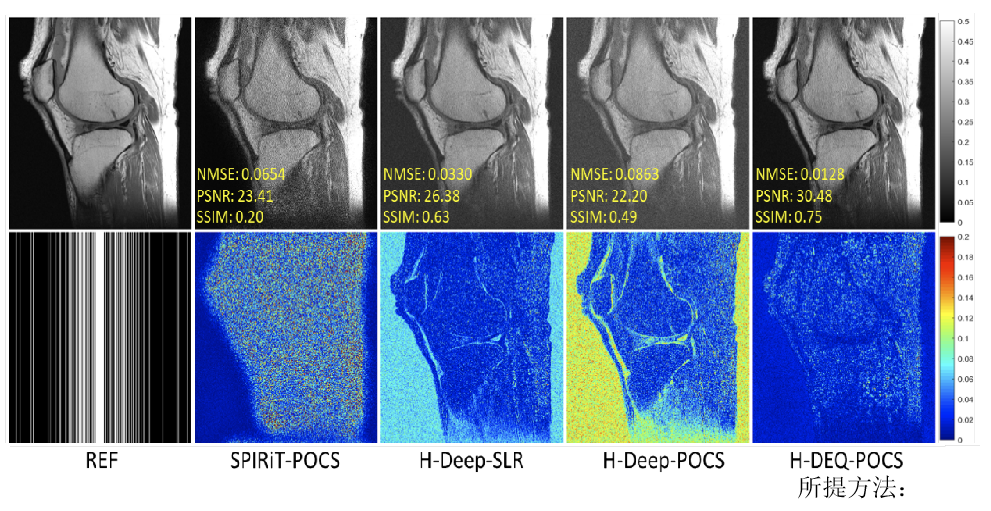

磁共振利用多通道线圈接收人体生理信号,多线圈的数据间具有很强的相关性。团队针对磁共振成像中全采数据难以取得的巨大挑战,提出利用线圈间数据相关性这一物理先验,来构建磁共振物理驱动的无监督深度神经网络成像模型,并分析了网络的误差上界,为成像可靠性给予保障。实验结果(图1)表明,该方法无需训练数据就能够重建出高质量图像,且效果与需要训练数据方法类似。研究成果发表在医学成像领域著名期刊Medical Image Analysis

图1. 5倍加速重建结果